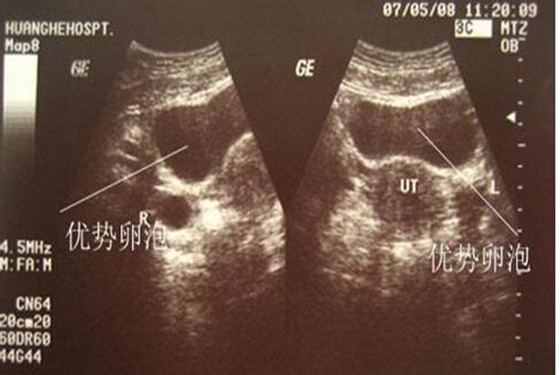

若要问卵泡监测什么时候做最合适,医生建议根据具体的月经周期进行监测,每个女性的月经周期有所不同,排卵的时间也各自有差异。卵泡监测一般在月经周期第9-10天时进行,每隔1-2天去医院用B超监测一次,医生通过几次B超检测后,就可以看到卵泡慢慢长大、成熟以及排卵的全过程。至于,优势卵泡什么时候会出现,这是因人而异的,通常月经周期28天的女性,在监测的第9-12天内优势卵泡会出现。

有的女性月经不规则,所以,她们的卵泡监测时间与月经规则的女性有所不同,对于月经不规则的女性来讲,卵泡监测时间应从月经第3-30天进行监测,中间不能间断或停止,因为女性的月经不规则,就无法确定卵泡期和月经期,唯一能做的就是长时间的监测卵泡,看看它具体的变化成长过程。